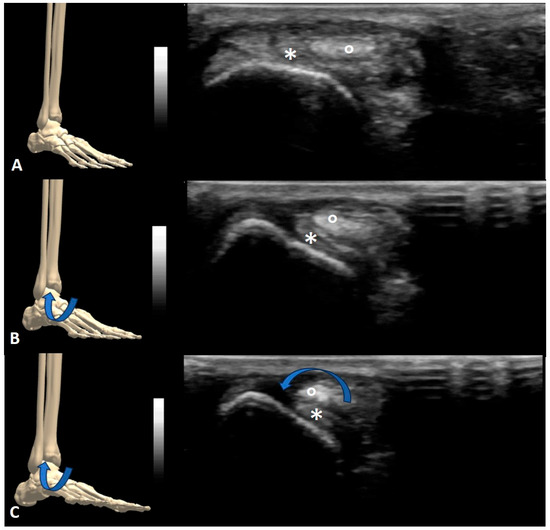

3. Results

4.1. Nerve Snapping

4.2. Tendon Snapping